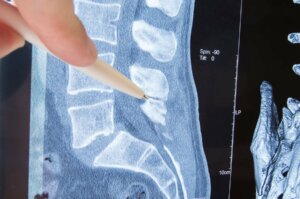

Co istotne, postawienie prawidłowej diagnozy radikulopatii wymaga wykonania rezonansu magnetycznego lub tomografii komputerowej.